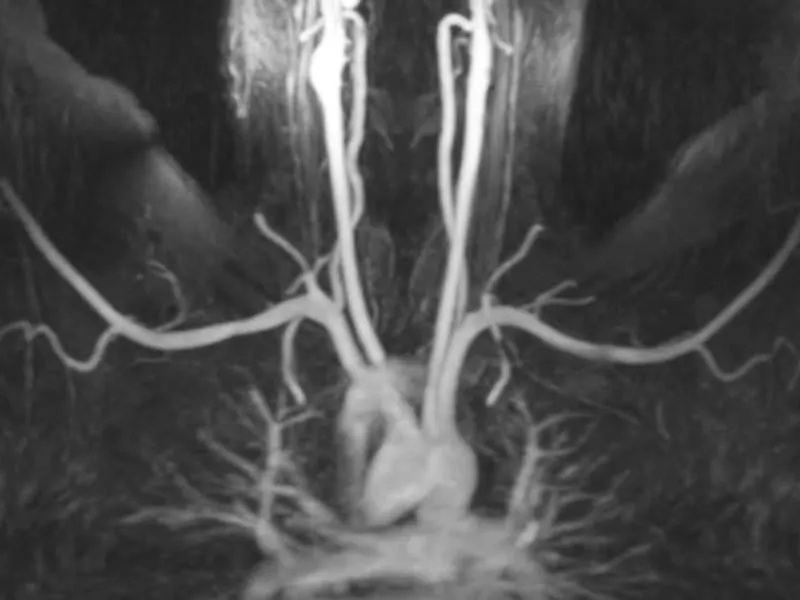

This image from a NeoVista® MRA demonstrates two important details. First, the image shows both subclavian arteries with good detail. Most imaging centers using standard injected gadolinium contrast material will achieve good quality on one side only. For example, Raptis, Thompson, et al published in 2016 that, “The intravenous catheter should be placed on the side opposite the symptoms…”, with the intent to image one side only. Most imaging centers can only consistently achieve good imaging quality on one side, and must avoid the symptomatic side. But what do they do if the patient has symptoms on both sides? The NeoVista® examination overcomes this limitation. One injection, one set of images, and excellent quality.

Second, not only are the arteries in this NeoVista® MRA bright, all other tissues are darkened as much as possible. While this darkening or suppression is fine for evaluating the arteries, there is no way to tell if extrinsic structures adjacent to the arteries are compressing the arteries. Since TOS is caused by extrinsic structures in the thoracic outlet, suppression of adjacent tissues creates a significant limitation. The NeoVista® examination acquires all essential imaging components in one comprehensive thoracic outlet syndrome test. Thus, the radiologist can match abnormal arteries seen only on these MRA images with abnormal adjacent structures seen only on other images without visualization of the arteries.